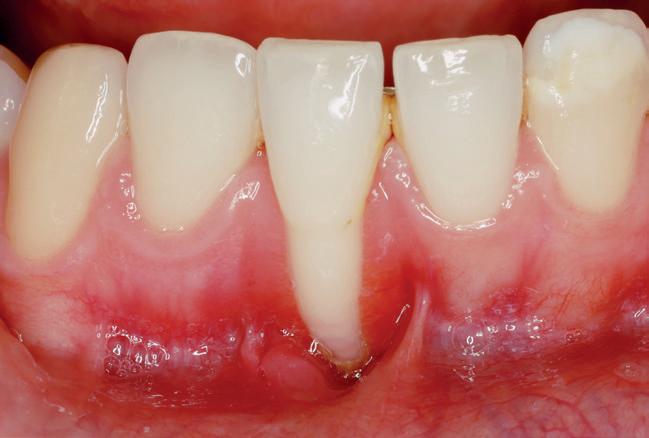

A recessão gengival é definida como o deslocamento da margem do tecido mole para uma posição apical à junção amelocimentária (JAC) (American Academy of Periodontology. Glossary of Periodontal Terms) e é uma característica clínica frequente em populações com bons e maus padrões de higiene oral (Loe et

al., 1992). A perda localizada de inserção com recessão gengival está localizada principalmente nos espaços interproximais em pacientes com inflamação periodontal induzida por placa e na superfície vestibular dos dentes em pacientes com altos padrões de higiene oral, podendo afetar superfícies radiculares simples ou múltiplas (Loe et al., 1992), (figs. 1 a 4).

Figs.1 a 4. Recessões gengivais.